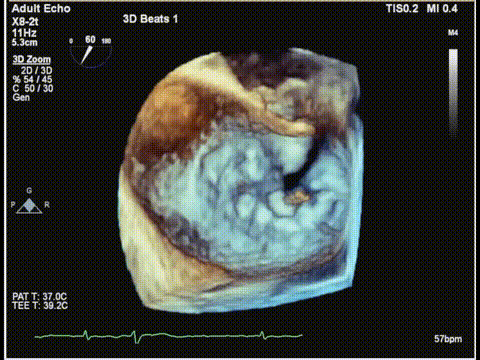

二尖瓣3D

二尖瓣3Dcolor